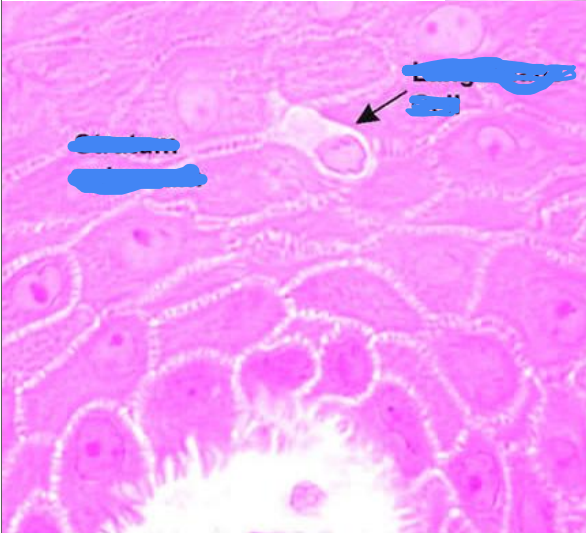

Where is this, and what is the arrow pointed at?

Stratum Spinosum

Langerhans cells

Identify the circled cell

Melanocyte (no distinct colour)

What is the circled cell?

Melanocyte

What is circled?

Identify the cell

Langerhans cell